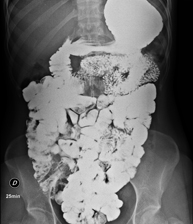

- Abdomen X-ray

An abdominal X-ray uses a small dose of radiation to obtain a two-dimensional image of the abdomen with its anatomical structures (stomach, small intestine, large intestine, liver, pancreas, kidneys, bladder, bony pelvis, etc.).

Prova diagnòstica que consisteix en obtenir imatges radiològiques en moviment de l'esòfag, estómac i duodè mitjançant l'ús de raigs X (fluoroscòpia) i d'un contrast opac baritat que s'administra per via oral. - Trànsit intestinal

Prova diagnòstica que consisteix en obtenir imatges radiològiques en moviment de l'esòfag, estómac, duodè i intestí prim mitjançant l'ús de raigs X (fluoroscòpia) i d'un contrast opac baritat que s'administra per via oral. - Ènema opac doble contrast

Prova diagnòstica que consisteix en obtenir imatges radiològiques de l'intestí gros (còlon i recte) mitjançant l'ús de raigs X. S'utilitza un contrast opac que s'administra a través del recte en forma d'ènema i també s'introdueix aire per expandir el còlon.